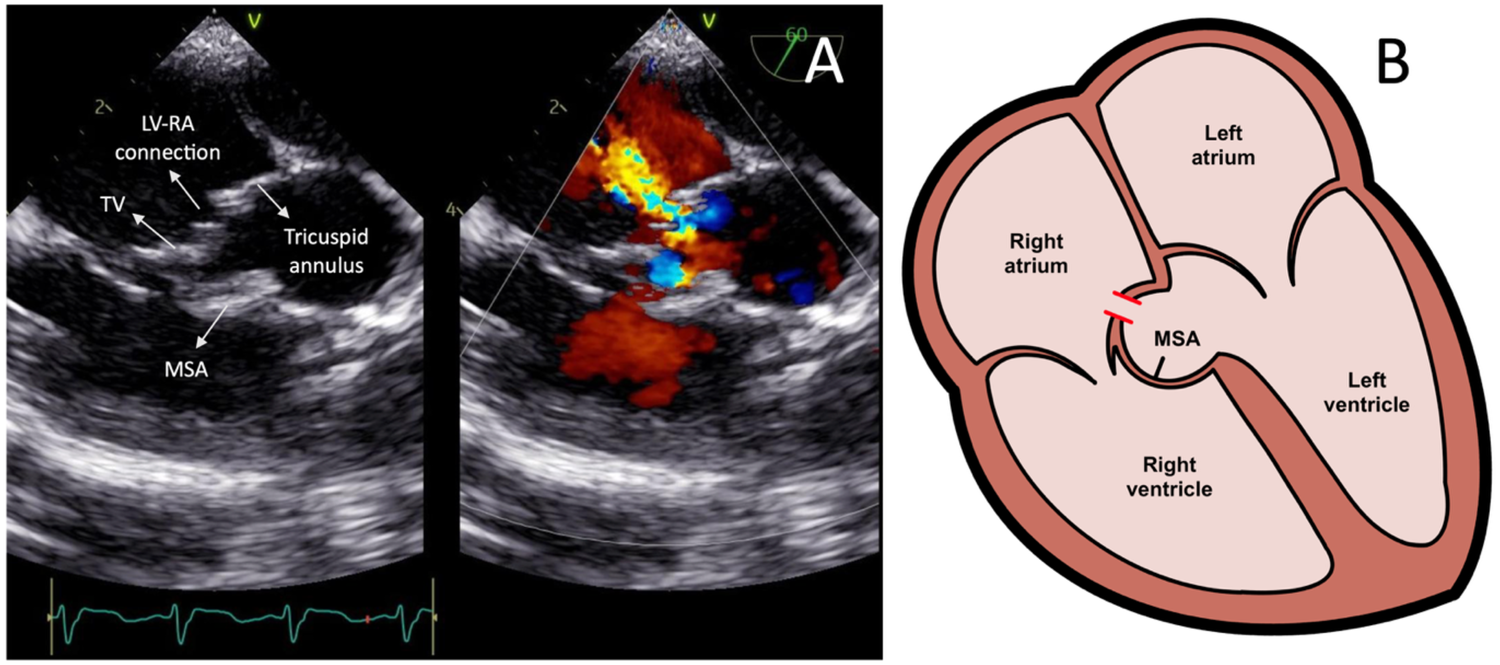

Transcatheter closure of the LV-RA connection was carried out in 2025 following the patient's parent's consent. Pre-procedural TEE showed a 4 mm defect in the septal leaflet of the tricuspid valve, initially misinterpreted as a residual VSD (Figure 2A), creating moderate shunt from the left ventricle to the right atrium. A residual membranous septal aneurysm (MSA) extending from the aortic region to the septal annulus of the tricuspid valve was also observed, without any evidence of a residual VSD shunt to the right ventricle (Figure 2B). Additionally, a small left-to-right ASD was identified. A TEE-guided tricuspid defect device closure was decided using Konar-MF VSD Occluder No. 8/6 mm.

Figure 2

(A) Transesophageal echocardiography images showing the left ventricle-right atrium connection prior to the device closure. (B) Heart illustration representing the left ventricle-right atrium connection from the tricuspid valve leaflet defect and associated membranous septal aneurysm. LV-RA, left ventricle-right atrium; MSA, membranous septal aneurysm; TV, tricuspid valve.